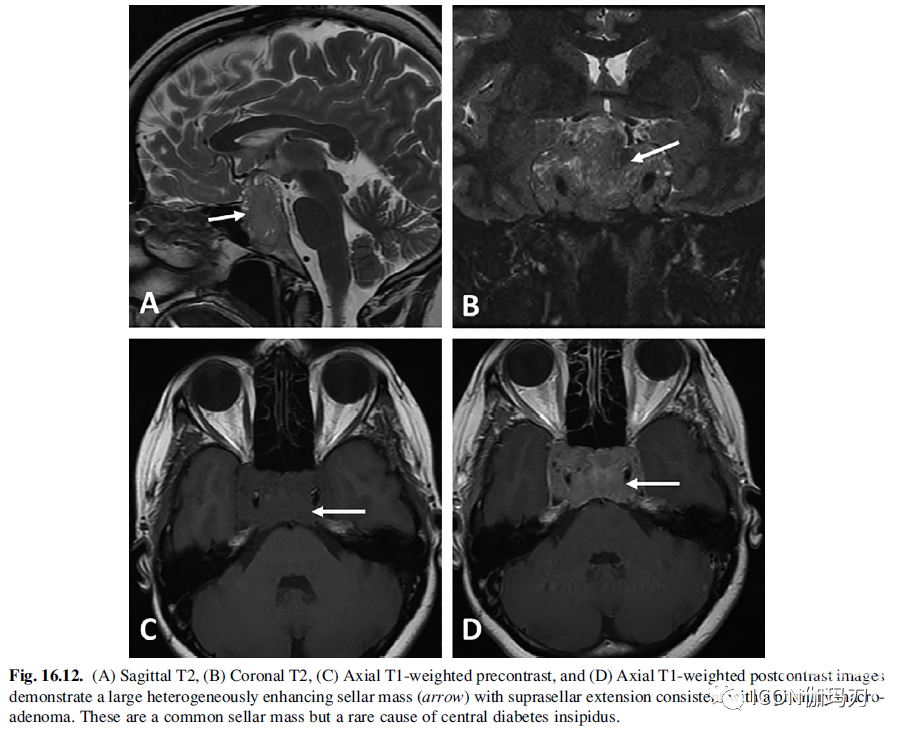

垂体腺瘤是鞍/鞍上最常见的肿瘤之一。它们经常引起漏斗部的肿块占位效应,但尽管如此,它们几乎从不引起CDI 。这可能与垂体大腺瘤缓慢进行性生长有关,其主要损伤垂体后叶的神经末梢,保留下丘脑中产生AVP的细胞体。随后AVP的分泌部位向漏斗部或正中隆起转移,阻止了CDI的发生。鉴于垂体腺瘤伴CDI的罕见性,应考虑其他诊断,如颅咽管瘤(CP)、Rathke裂囊肿(RCC)或转移瘤。腺瘤的类型影响MRI特征(图16.12)。在80% - 90%的患者中,垂体大腺瘤在T1加权序列上低于正常垂体前叶。其余病灶在T1上呈等信号,仅在T1增强成像上可检测到。很少出现T1高信号,可能继发于出血,这在泌乳素瘤中更为常见。大约33% - 50%的微腺瘤T2加权成像呈高信号,超过80%的泌乳素微腺瘤T2信号增高。66%的患者的分泌GH的腺瘤是等信号或低信号。在增强的T1加权图像上,微腺瘤表现为低信号,而其他正常腺体则表现为强而均匀的强化。如果腺瘤很小,则可能是在标准图像和延迟图像上不明显,30 - 40分钟增强可能显示腺瘤本身的延迟增强。另外,垂体的DCE可以显示微腺瘤不同的一过性强化,与背景中的正常垂体相比,微腺瘤呈低信号。

图16.12.(A)矢状位T2, (B)冠状位T2, (C)轴位t1加权增强成像,和(D)轴位T1加权增强成像显示一个巨大的不均匀增强鞍区肿块(箭头),向鞍上延伸,符合垂体大腺瘤。这是一个常见的鞍区肿块,但是一种罕见的导致中枢性尿崩症的原因。